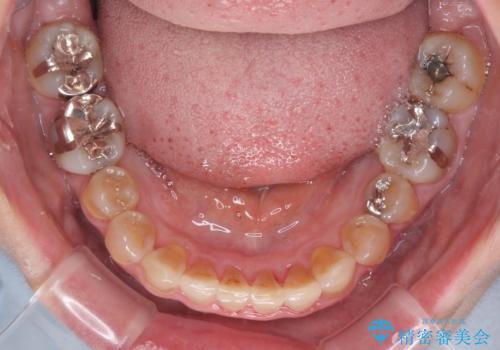

- 前歯のデコボコと、顎に負担のかかる歯並びを改善したいとのことで来院された患者様です。

うまく歯ぎしりができず、強く食いしばりをしてしまう咬み合わせであったため、奥歯に非常に負担がかかっていました。

インビザラインを用いて前歯のデコボコを改善するとともに、奥歯の咬み合わせを変えてスムーズに歯ぎしりできるように排列していくこととしました。

可能であれば上下正中を合わせ、左右の咬み合わせも改善したかったのですが、骨格的な左右差が大きかった上に、インビザラインでは限界があり、達成できませんでした。

それでも奥歯の負担を改善することができました。